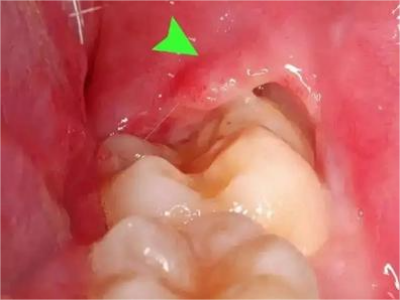

阻生牙是指由于邻牙、骨或软组织的阻碍而只能部分萌出或完全不能萌出,且以后也不能萌出的牙。引起牙阻生的成因,主要是由于颌骨缺乏足够的空间容纳全部恒牙。常见的阻生牙为下颌第三磨牙、上颌第三磨牙及上颌尖牙。

阻生牙可反复引起冠周炎,或引起邻牙牙根吸收和破坏,位置不正,不能完全萌出,好发部位是上、下颌第三磨牙。